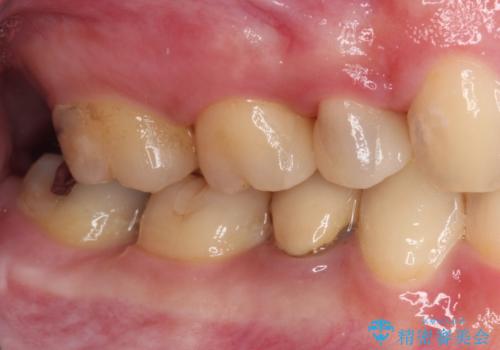

まだ銀歯が残っていますが、大きく目立つ銀歯をセラミックに置き換えることができ、人前で口を開けることを気にしなくなりました。

補綴治療中の後戻り対策をしっかりと行ったことで、歯列全体をきれいに整えることができました。